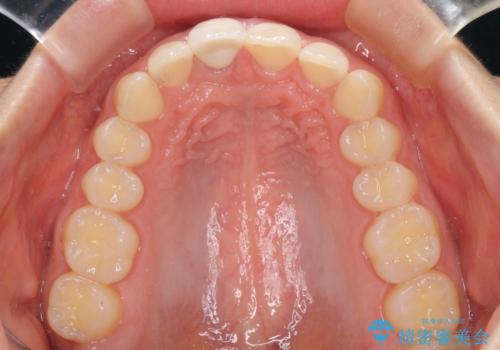

- 中学生の時にぶつけて神経を取り除いた前歯の変色が気になるとのことで来院された患者様です。

レントゲン写真より、歯根の炎症が認められなかったため、ファイバーコアによる土台築製後、オーダーメイドタイプのオールセラミッククラウンにて補綴することとしました。

あっという間に気になっていた変色が解決し、早く治療を始めれば良かったとおっしゃっていました。

オーダーメイドタイプのクラウンを選択いただいたので、まるで天然の歯と見間違うほど自然に仕上がり、患者様には大変満足していただきました。